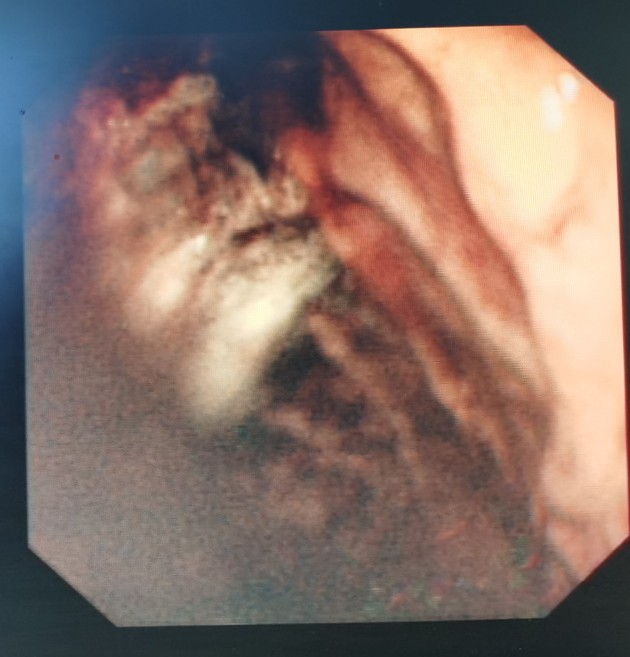

胃镜下看到的贲门肿瘤

从食管向胃方向看到的贲门肿瘤

贲门肿瘤已经快完全堵塞食管了